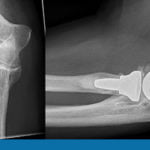

Артроз

Характеризуется разрушающим действием на коленные хрящи и сухожилия, в результате чего они деформируются. Болевые ощущения возникают при ходьбе даже на незначительные расстояния, при подъеме со стула после длительного сидения. В состоянии покоя они исчезают. Диагностика артроза коленного сустава выполняется проведением рентгеновского обследования, артроскопии, ультразвукового исследования костных структур нижних конечностей.